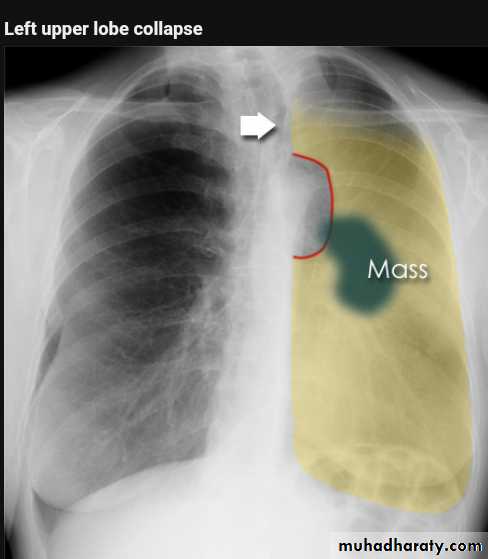

Left upper lobe collapse has distinctive features but can be challenging to identify on chest radiographs by the uninitiated.

Radiographic features

The left upper lobe collapses anteriorly becoming a thin sheet of tissue apposed to the anterior chest wall, and appears as a hazy or veiling opacity extending out from the hilum and fading out inferiorly . It thus reverses the normal slight increase in radiographic density seen as you move down the lung (due to increased thickness of the chest soft tissues).

Parts of the normal cardiomediastinal contour may also be obliterated where the left upper lobe, particularly the lingula abut the left heart border. The anterior parts of the aortic arch are also often obliterated from view.

In some cases the hyperexpanded superior segment of the left lower lobe insinuates itself between the left upper lobe and the superior mediastinum, sharply silhouetting the aortic arch and resulting in a lucency medially. This is known as the luftsichel sign.

The left hilum is also drawn upwards, resulting in an almost horizontal course of the left main bronchus and vertical course of the left lower lobe bronchus.

Radiology of BGCA

The appearance depends on the location of the lesion.1.The more central lesions may merely appear as a bulky hilum, representing the tumor and local nodal involvement the lesion is irregular in outline have spiky or sun ray spiculation .

2.Lobar collapse may be seen due to obstruction of a bronchus. When the right upper lobe is collapsed and a hilar mass is present, this is known as the Golden S sign.

3.A more peripheral location may appear as a rounded or spiculated mass. Cavitation may be seen as an air-fluid level , more to be large cell CA .